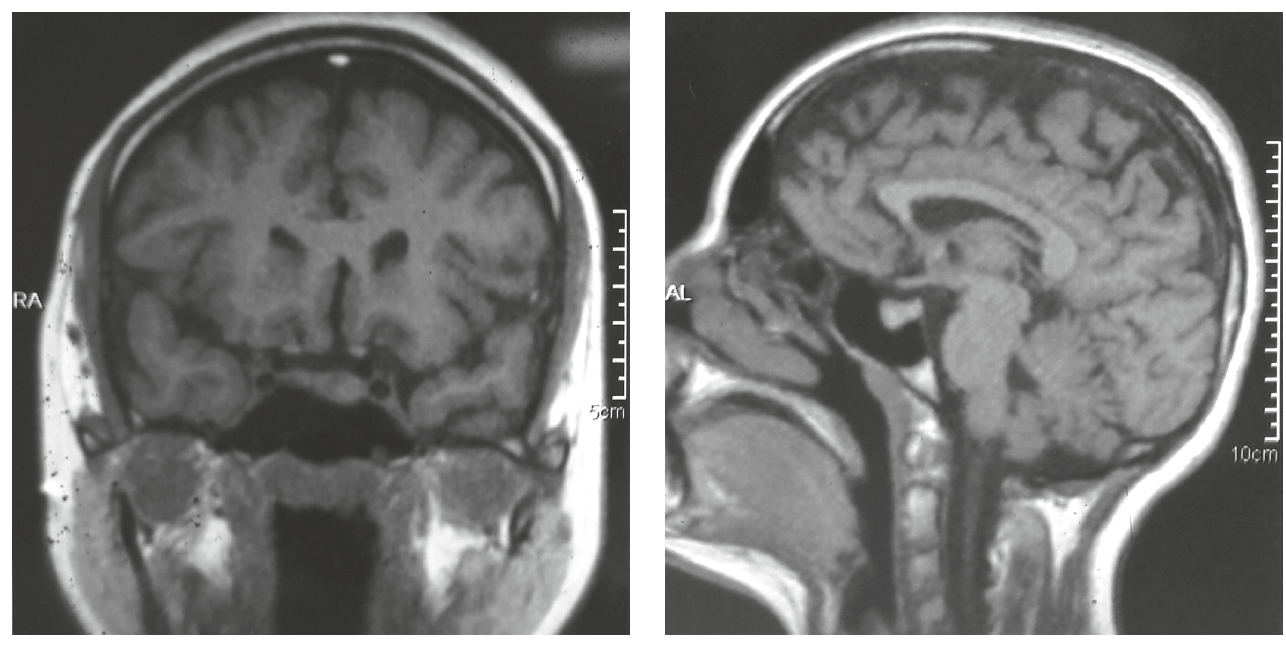

Пациентка Р., 36 лет, обратилась с жалобами на нарушение менструального цикла по типу олигоменореи в течение года, головные боли, нарушение зрения.

При осмотре у пациентки нормальное телосложение, ИМТ=24,2 кг/м2, при осмотре молочных желез лактореи выявлено не было. При лабораторном обследовании уровень ПРЛ в сыворотке крови при обращении – 1500 мЕд/л. Проведено МРТ головного мозга, (рис. 2), выявившее эндосупралатероселлярную макроаденому гипофиза размерами 18 × 22 × 19 мм. Пациентка консультирована офтальмологом. Данных за хиазмальный синдром не выявлено.

Рис. 2. МРТ головного мозга пациентки Р. с аденомой гипофиза

Пациентке установлен диагноз: Эндосупраселлярная аденома гипофиза, пролактинома. Вторичная аменорея. Назначено лечение каберголином (Достинексом) в дозе 0,5 мг в неделю.

На фоне проводимого медикаментозного лечения уровень ПРЛ нормализовался, пациентка отметила восстановление менструального ритма, уменьшение частоты возникновения головных болей. При обследовании через 6 мес по данным МРТ головного мозга размеры опухоли без отрицательной динамики, отмечено снижение плотности образования, расцененное как положительная динамика на фоне лечения. Продолжает прием каберголина 0,5 мг в неделю.